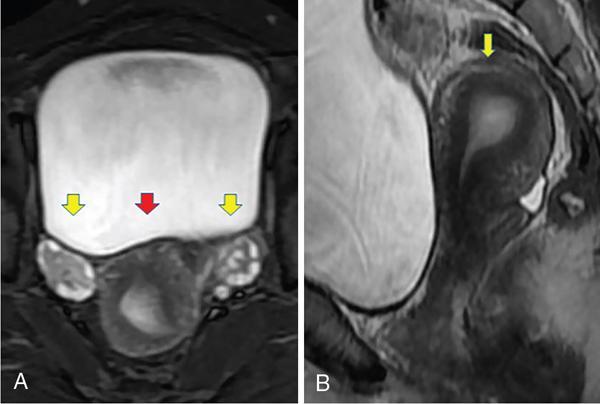

IMAGING ANATOMY OF MALE REPRODUCTIVE SYSTEM Ganesh Rajagopal The male reproductive system is formed by testes, ejaculatory ducts, seminal vesicles (SVs), prostate and penis. Various diagnostic imaging modalities like ultrasound (US), computed tomography (CT), magnetic resonance imaging (MRI) and positron emission tomography (PET) are helpful in the diagnostic evaluation of male reproductive system. Various indications for imaging may include acute scrotum (testicular torsion, trauma and epididymo-orchitis), scrotal swelling (hydrocele, spermatocele, idiopathic scrotal wall oedema and scrotal abscess) and infertility. US and MRI are the commonly used imaging modalities in male reproductive system which complement each other. CT is not very useful due to poor contrast resolution. Ultrasound imaging (US) with a high-frequency linear (7.5–10 MHz) transducer probe has become the imaging modality of choice for scrotal evaluation. Scrotal US is an excellent imaging modality as it can demonstrate abnormalities in testis as well as in paratesticular structures. Scrotal wall is formed by the skin, superficial fascia, dartos muscle, the external spermatic fascia, cremasteric fascia and the internal spermatic fascia. The scrotum is divided into two cavities by a median raphe. This multilayered scrotal wall is poorly delineated in US and MRI, it is typically hypointense on both T1- and T2-weighted images. Testes are paired organs, located normally in scrotal sac, suspended by the spermatic cords. Each testis is examined in orthogonal transverse and longitudinal planes, with both grey scale and colour Doppler modes, to assess its volume and blood flow. Volume of testis is calculated by length × height × width × 0.71. A total volume (both testes) of >30 mL and a single testicular volume of 12–15 mL is generally considered normal for adults. Testes are supplied by the testicular arteries, which arise from the aorta and enter the spermatic cord at deep inguinal ring to reach the upper pole of testis. Pampiniform plexus of veins surrounds the testis and appears as a serpiginous tubular structure posterior to it, measuring >2–3 mm in diameter. Testes are oval shaped, with homogeneous echotexture on grey scale US. Along with the epididymis, they are surrounded by an echogenic capsule, known as the tunica albuginea. Tunica albuginea is covered by tunica vaginalis, which is a remnant of the processus vaginalis and both represent closed sac of peritoneum with two layers. This tunica albuginea is seen extending into posteromedial testis and form the mediastinum testis (Fig. 11.2.1.1), which consists of ducts, nerves and blood vessels. The mediastinum testis is seen as a thin echogenic band. Rete testis is formed by the convergence of seminiferous tubules, seen as a hypoechoic area adjacent to mediastinum testes. The epididymis is a comma-shaped, elongated structure placed at the posterior border of the testis, which drains the efferent ductules (Fig. 11.2.1.2). It has head, body and tail. The head overlies the superior pole of the testis and is isoechoic or slightly hyperechoic whereas, the body and tail are located behind and along the inferior pole and are usually isoechoic. The tail of the epididymis continues into vas deferens (VD), which along with the nerves, lymphatic and vascular structures, forms the spermatic cord (Fig. 11.2.1.3). The spermatic cord appears as an echogenic band in the inguinal canal. The normal adult testis is a homogeneous oval structure that appears hyperintense on T2-weighted sequences and hypointense–isointense on T1-weighted images (Fig. 11.2.1.4). The tunica which surrounds the testis is hypointense T1- and T2-weighted sequences. Epididymis is isointense on T1-weighted images but hypointense on T2-weighted images compared to testis (Fig. 11.2.1.5). Both testicles and epididymis enhance after intravenous administration of gadolinium (Gd) MR contrast agents. Prostate, though visualized by transabdominal scan is better assessed by transrectal high frequency (7.5–10 MHz) ultrasound transducer (TRUS) with patient in left lateral decubitus position. The prostate gland is divided into the anterior fibromuscular stroma (devoid of glandular tissue), transition zone, central zone, periurethral zone and peripheral zone. The base of the prostate is located superiorly and contiguous with the bladder neck whereas, the apex of the prostate is located at the inferior aspect continuous with the striated muscles of the urethral sphincter. The neurovascular bundle is seen to course near the posterolateral aspect of prostate, which is a preferential route of tumour spread. The prostate appears as a cone-shaped organ and shows uniform low echogenicity (Fig. 11.2.1.6). The outer gland (central and peripheral zones) is generally more echogenic than the inner gland. The transition and central zones of the prostate have similar MR signal intensity and cannot be differentiated, hence, are collectively referred as the central gland. On T2-weighted MR images, the normal peripheral zone is homogeneously hyperintense, whereas the central gland tissue is typically hypointense or isointense compared to the skeletal muscle (Fig. 11.2.1.7). The capsule and the anterior fibromuscular stroma appear hypointense on T2-weighted MR images. The SVs are seen as septate tubular cystic structures, appearing uniformly anechoic in US, above the prostate with distal portion of VD is seen medial to it. The duct of SV and VD joins to form the ejaculatory duct, which drains into the prostatic urethra via verumontanum. SVs show ‘bow-tie’ appearance in transversal scans, and a club or tennis-racket shape in longitudinal scans (Fig. 11.2.1.8). On MR, SVs are seen as elongated fluid-containing structures with thin septa, which is hypointense on T1 and hyperintense on T2-weighted MR images (Fig. 11.2.1.9). The VD is seen as a tubular structure with low signal intensity in both T1- and T2-weighted images, on either side. The dilated distal portion of VD (ampulla), appears hyperintense on T2-weighted images, similar to that of the SV due to the fluid content (Fig. 11.2.1.10). The penis, being a superficial organ, is usually examined with US, although MRI is reserved as problem solving modality. The penile body contains two paired muscles – corpora cavernosa and a corpus spongiosum. The former performs as a main erectile body while the latter contains the penile urethra (Fig. 11.2.1.11). Dartos fascia forms the outer layer and the Buck fascia forms the inner layer, which contain the deep dorsal vein (DDV) and a paired dorsal neurovascular bundle. The corpus spongiosum and corpora cavernosa are of high signal intensities on T2-weighted MR images and intermediate-low signals on T1-weighted MR images. The tunica albuginea being a fibrous sheath, surrounds all the three muscles, is hypointense on all sequences (Fig. 11.2.1.12). IMAGING ANATOMY OF FEMALE REPRODUCTIVE SYSTEM Saranya The female reproductive system comprises of uterus, cervix, fallopian tubes, ovaries, vagina and vulva. Ultrasonography (transabdominal and transvaginal) is the primary imaging modality of choice for imaging the female pelvis. Computed tomography (CT) is less often used for pelvic imaging. It provides a quick and systematic overview with coverage of the abdomen in the same session. Hence, CT is well suited for staging pelvic cancers and for imaging gynaecologic and nongynaecologic diseases presenting with acute abdominal pain. Pelvic anatomy is well demonstrated by magnetic resonance imaging (MRI). The contrast resolution of T2-weighted images form the basis for superb tissue characterization of MRI. Uterus is a thick-walled fibromuscular organ composed of myometrium and endometrium. It has two major divisions, namely, the body (corpus) and cervix. The fundus lies above the ostia of fallopian tubes. The normal uterus measures between 5 and 9 cm in length and is in an anteverted position, in relation to the urinary bladder. The myometrium shows three layers on USG, a compacted thin, hypoechoic inner layer forms subendometrial halo, a thicker, homogenously echogenic middle layer and a thinner, hypoechoic outer layer (peripheral to arcuate vessels). The appearance of the endometrium varies with the phase of the menstrual cycle. It appears as a thin echogenic line early in the proliferative phase and shows hypoechoic thickening (4–8 mm) as proliferative phase progresses. It shows a triple layer (sandwich or trilaminar) appearance in the mid cycle and may measure up to 12–16 mm. During secretory phase after ovulation, the layers are seen hyperechoic due to the increasing complexity of glandular structure and secretions (Fig. 11.2.2.1). Postmenopausally, the endometrium decreases in thickness. Endometrial thickness of 5 mm is taken as cut-off. Women on hormonal therapy acceptable endometrial thickness is up to 8 mm. Three-dimensional US permits multiple views to be reconstructed from a single sweep through the uterus. Sonohysterogram is the study of choice for detailed evaluation of the endometrial cavity pathologies. The cervix begins at the inferior narrowing of the uterus (isthmus) at the internal os, which is identified by the entrance of uterine vessels. It has supravaginal and vaginal portions. It is 3–4 cm long and shortens after childbirth. In premenarche women, cervix is larger than corpus, forming approximately 2/3 of the uterine mass. During menarche, there is preferential growth of the corpus and in nulliparous women, corpus and cervix are roughly equal, whereas in parous woman, corpus forms approximately 2/3 of the uterine mass. Uterus is an extraperitoneal organ. The peritoneum extends over urinary bladder dome to anterior uterus, forming anterior cul-de-sac (vesicouterine pouch) and posteriorly, the peritoneum extends more inferiorly to the upper portion of vagina, forming the posterior cul-de-sac (pouch of Douglas, rectouterine pouch), which forms the most dependent portion of the female pelvis. Supporting ligaments of the uterus comprise mainly of broad ligaments, which extend laterally to the pelvic wall and round ligaments, which arise from uterine cornu near fallopian tubes to course anteriorly, pass through the inguinal canal to insert on the labia majora. Connective tissue thickening at the base of the broad ligament forms the uterosacral ligaments posteriorly, cardinal ligaments laterally and vesicouterine ligaments anteriorly. CT examination displays the uterus as a triangular or ovoid soft tissue structure behind the urinary bladder (Fig. 11.2.2.2). Following the administration of intravenous contrast, there is enhancement of myometrium that helps to delineate the endometrium. The vagina, cervix and corpus can be differentiated by morphological characteristics and enhancement pattern. The uterine corpus is typically triangular, whereas cervix is more rounded. The vagina has an appearance of flat rectangle at the level of fornix. The broad ligament and round ligaments are seen coursing laterally and anteriorly, respectively. The main source of vascular supply to uterus is from the uterine arteries. The uterine arteries pass within the broad ligament to enter the uterus, adjacent to the lateral fornices. The uterine artery passes over the ureter at the level of the cervix. Then it courses superiorly, along the lateral margin of the uterus and anastomoses with the ovarian artery. Uterine arteries give rise to arcuate arteries, which run in the outer third of myometrium. Radial arteries extend through the myometrium, which terminate as spiral arteries in the endometrium. The venous system parallels the arterial system, forms a complex venous network in the parametrium and drains to the iliac veins. Middle and lower thirds of the uterus are drained by obturator, parametrial and paracervical lymph nodes. Lymphatic drainage from the upper corpus and fundus goes to the common iliac and paraaortic lymph nodes. MRI provides a more comprehensive view of the uterine anatomy. On MRI, the uterus and cervix show uniform low to intermediate signal on T1-weighted images. On T2-weighted images, uterus shows three distinct zones, namely high signal endometrium, low signal junctional zone and intermediate signal myometrium (Fig. 11.2.2.3). The normal thickness of the junctional zone varies from 2 to 8 mm. A thickness of 9 to 12 mm is equivocal and greater than 12 mm is abnormal. Both endometrium and junctional zone become thin with oral contraceptive intake. Endometrial atrophies and the junctional zone is absent in postmenopausal women. The endocervical canal shows high signal on T2-weighted images, whereas cervical stroma shows low signal, contiguous with the junctional zone. An outer layer of intermediate signal smooth muscle is present. Nabothian cysts representing obstructed, mucous secreting glands are commonly seen as low signal on T1-weighted images and high signal on T2-weighted images. Parametrium shows low to intermediate signal intensity on T1-weighted images and variable signal intensity on T2-weighted images. The round ligaments and uterosacral ligaments show low signal intensity, cardinal ligaments and associated venous plexuses show high signal intensity on T2-weighted images. Ovaries are located posterolateral to the body of the uterus between the uterus and the pelvic sidewall. The internal iliac vessels lie immediately posterior to the ovary. Exact position is variable due to the laxity in the ligaments, parity, uterine size and position. On USG, medulla of the ovaries is mildly hyperechoic compared to the hypoechoic cortex. Developing follicles appear anechoic (Fig. 11.2.2.4). Corpus luteum may have a thick, echogenic ring and haemorrhage is common.